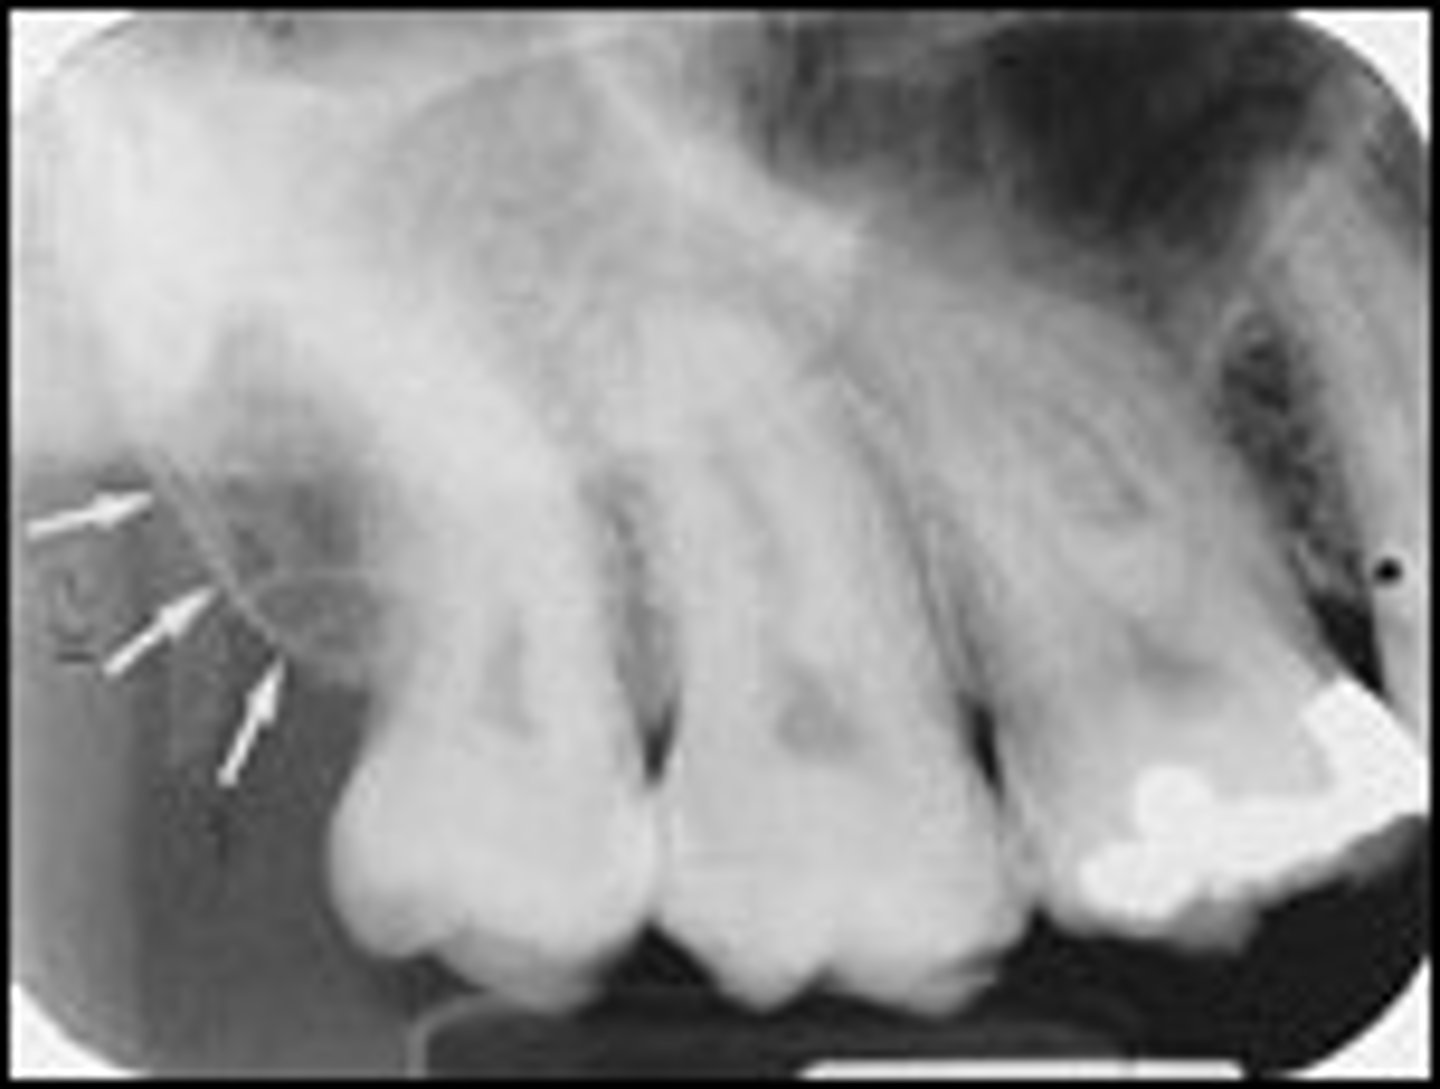

Nutrient canals

What is the radiolucent structure seen here?